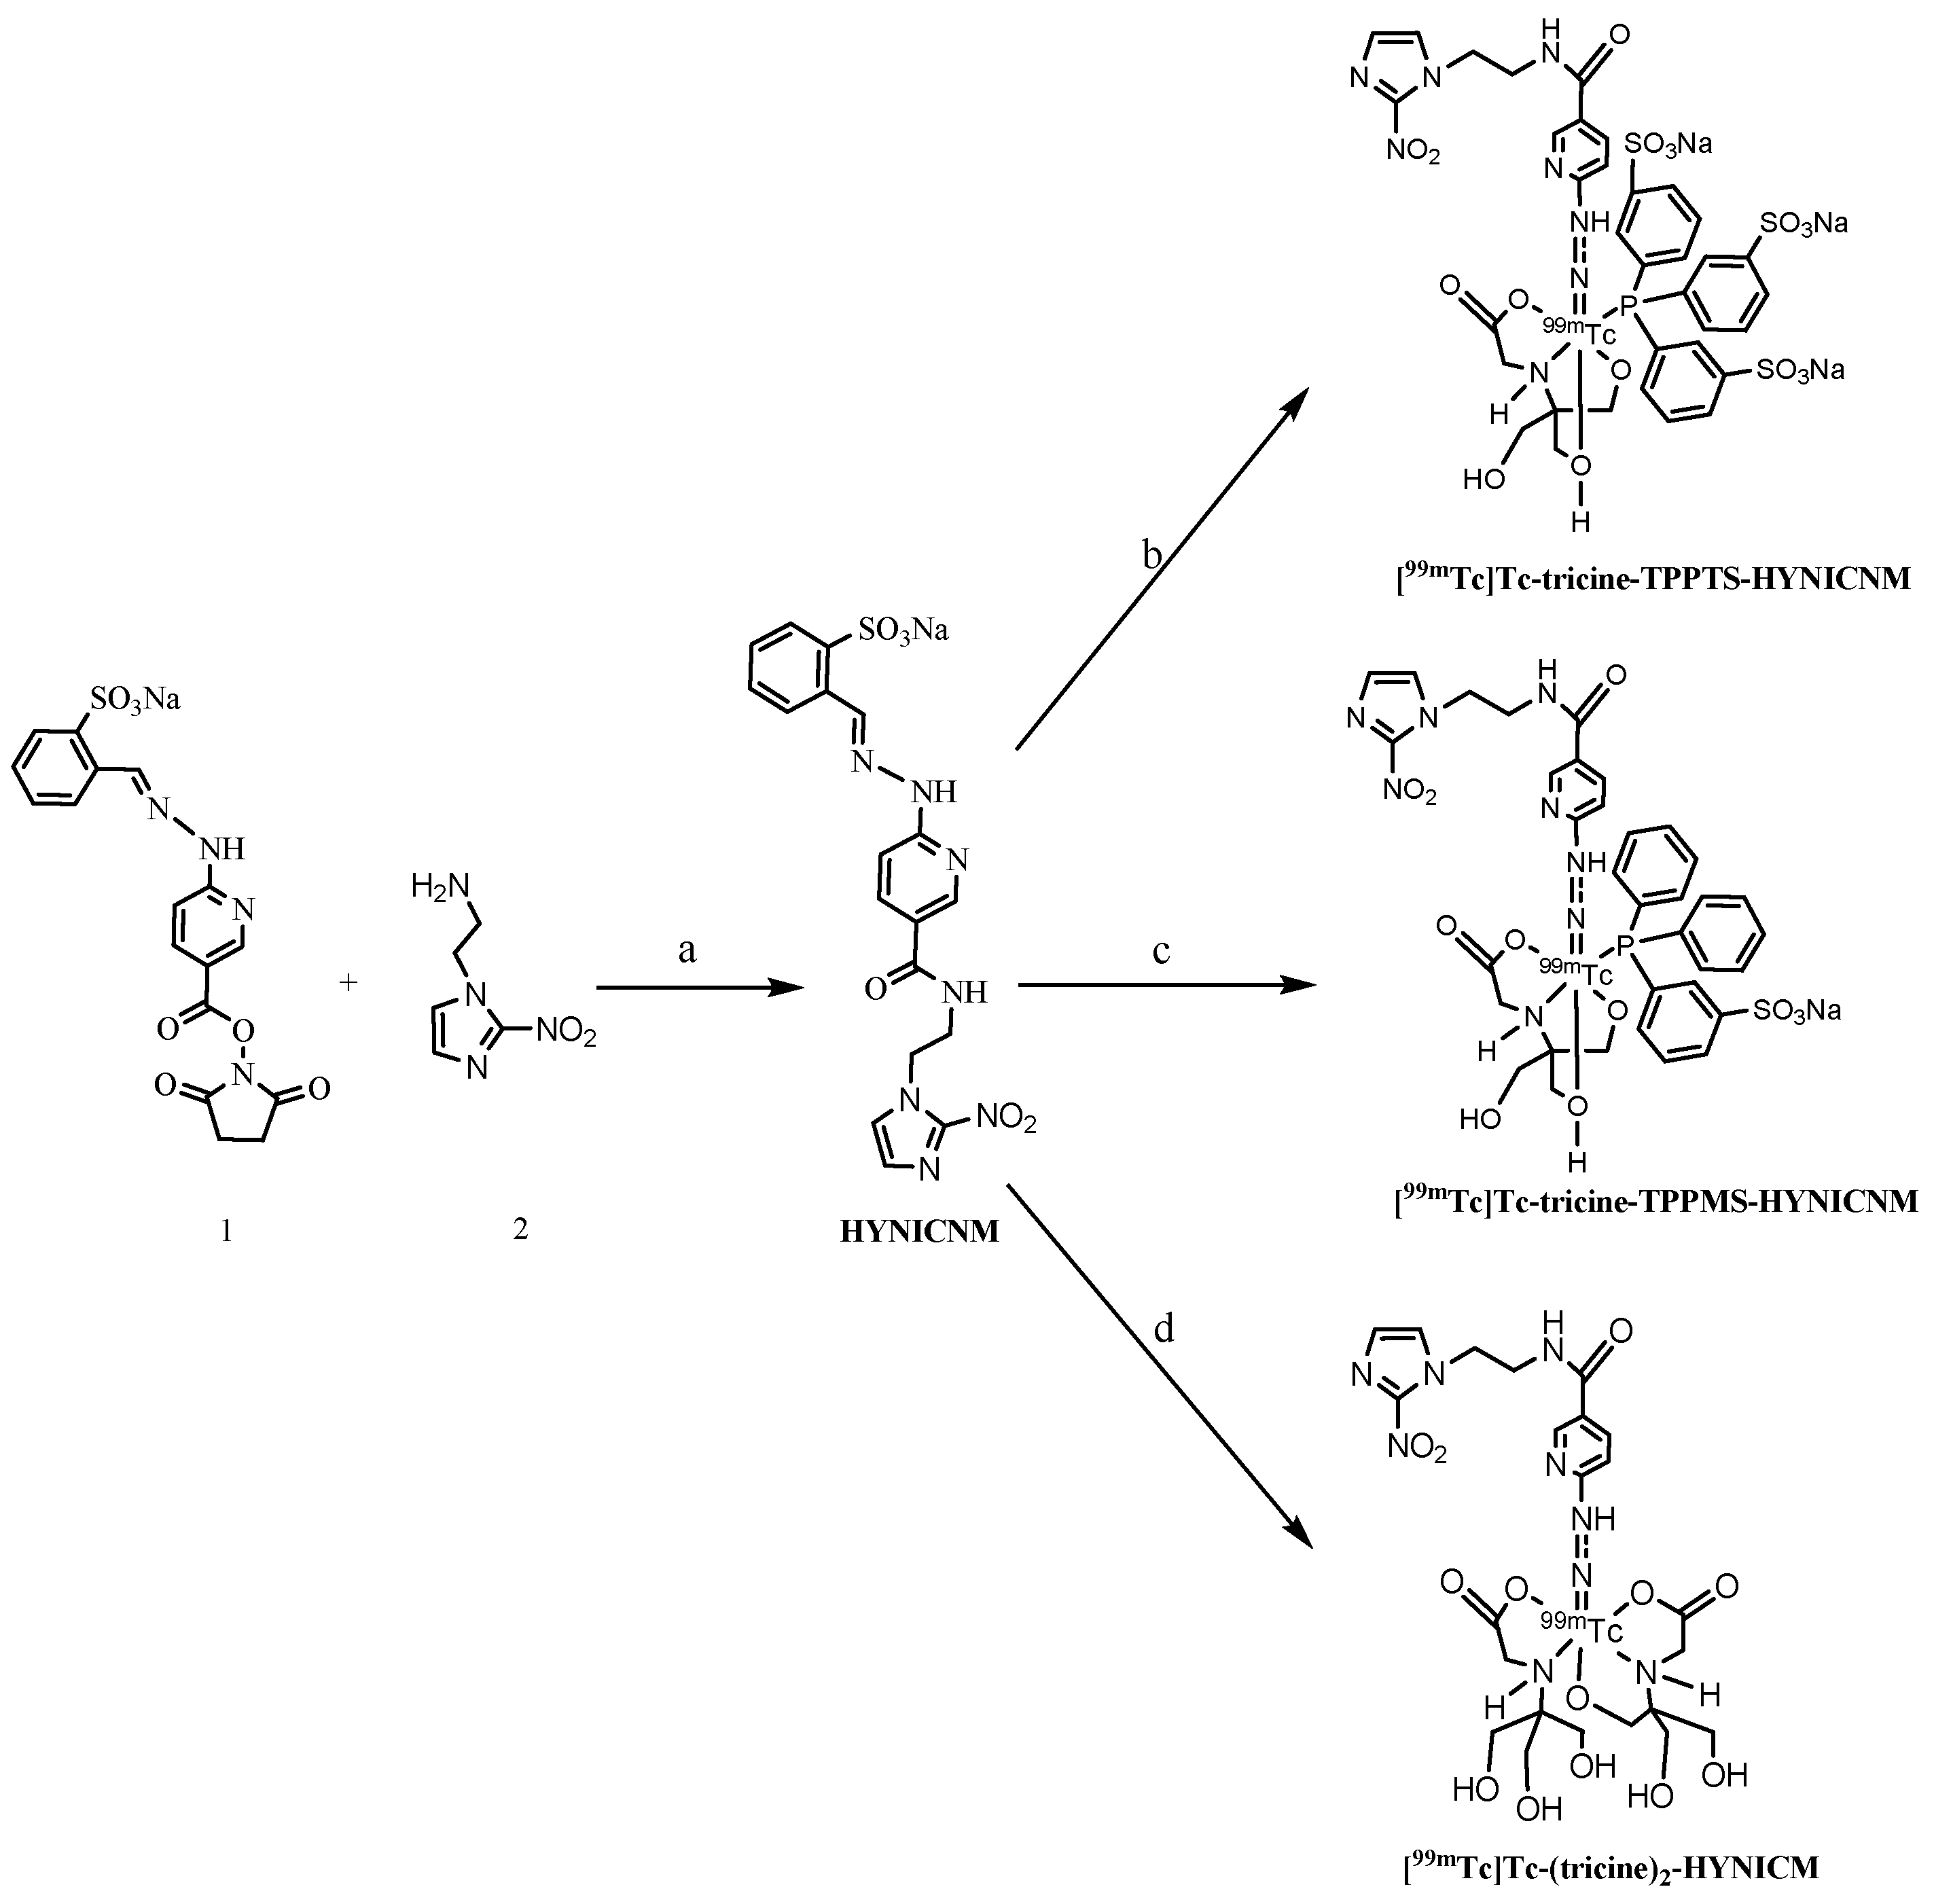

2.1. Synthesis of HYNICNM

4.2. Synthesis of HYNICNM